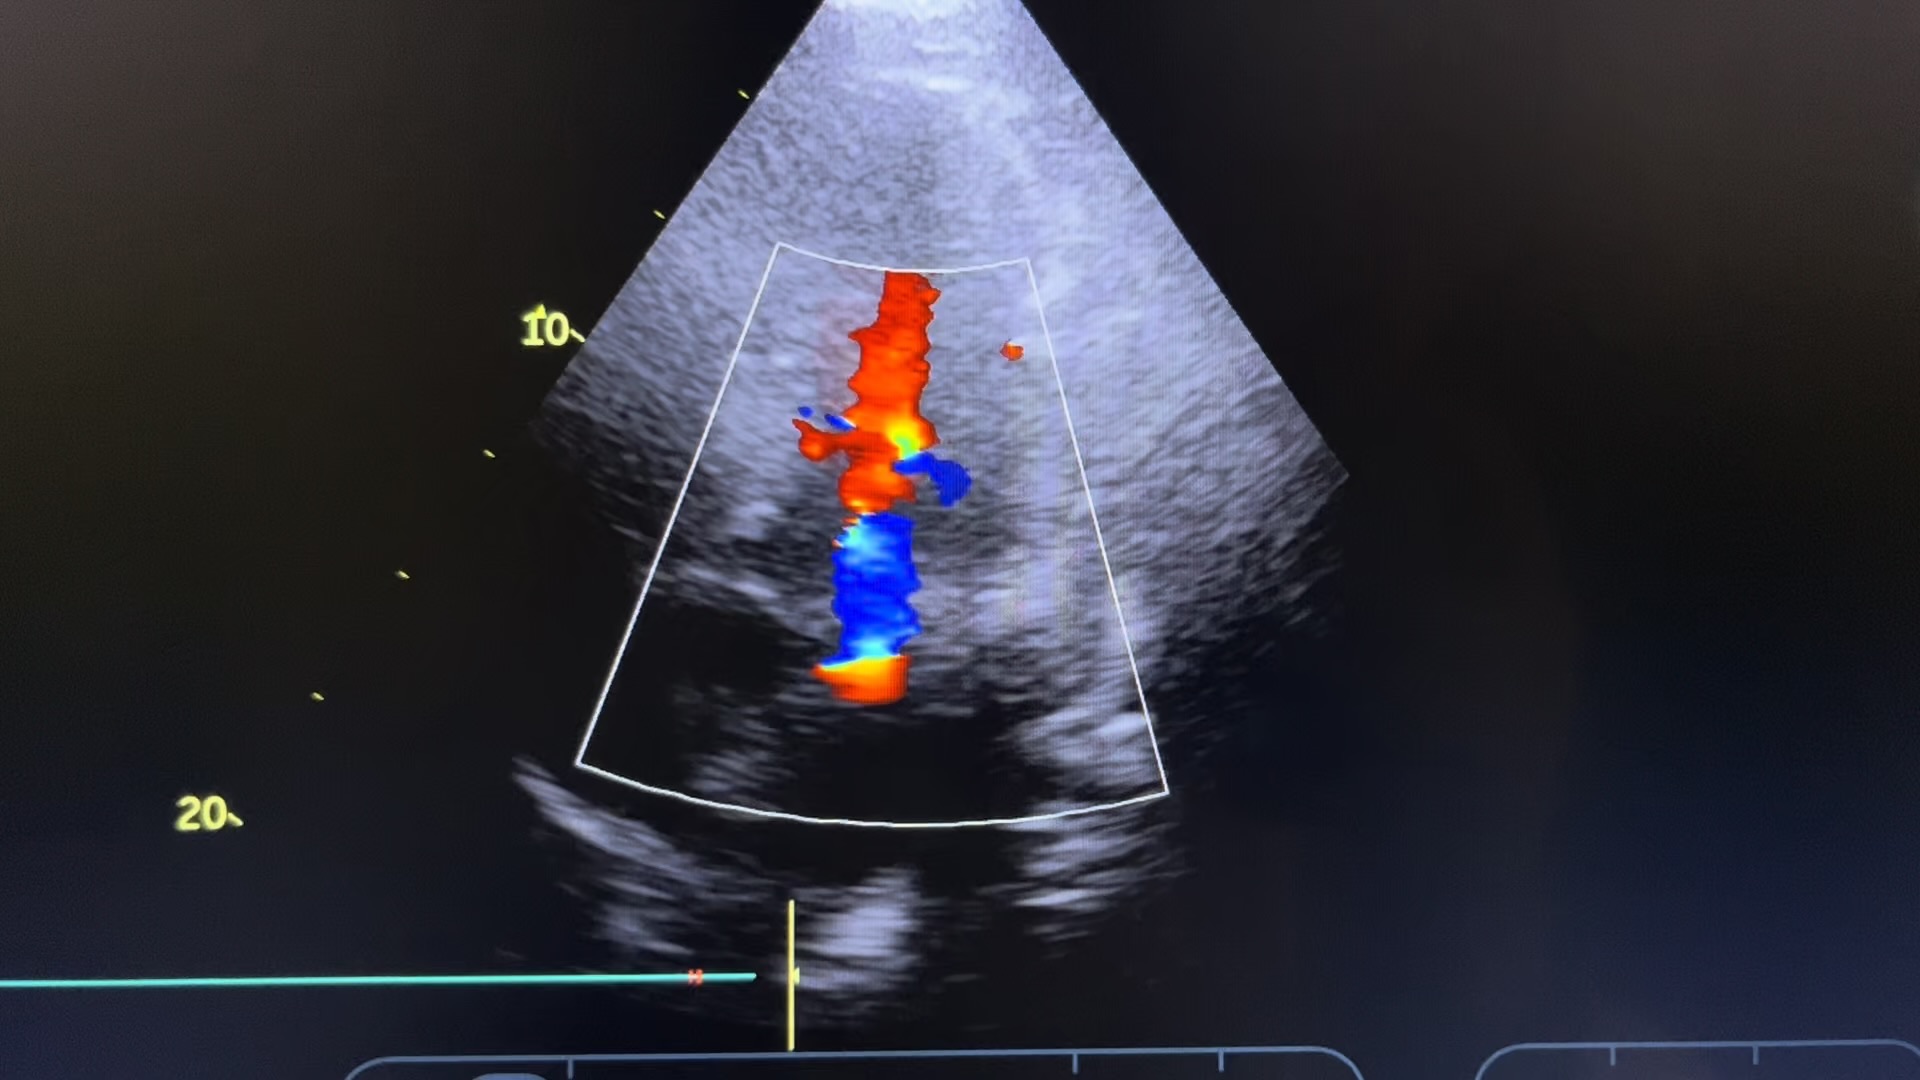

虽然不清楚,但这就是短轴,

往返频谱

红蓝交替